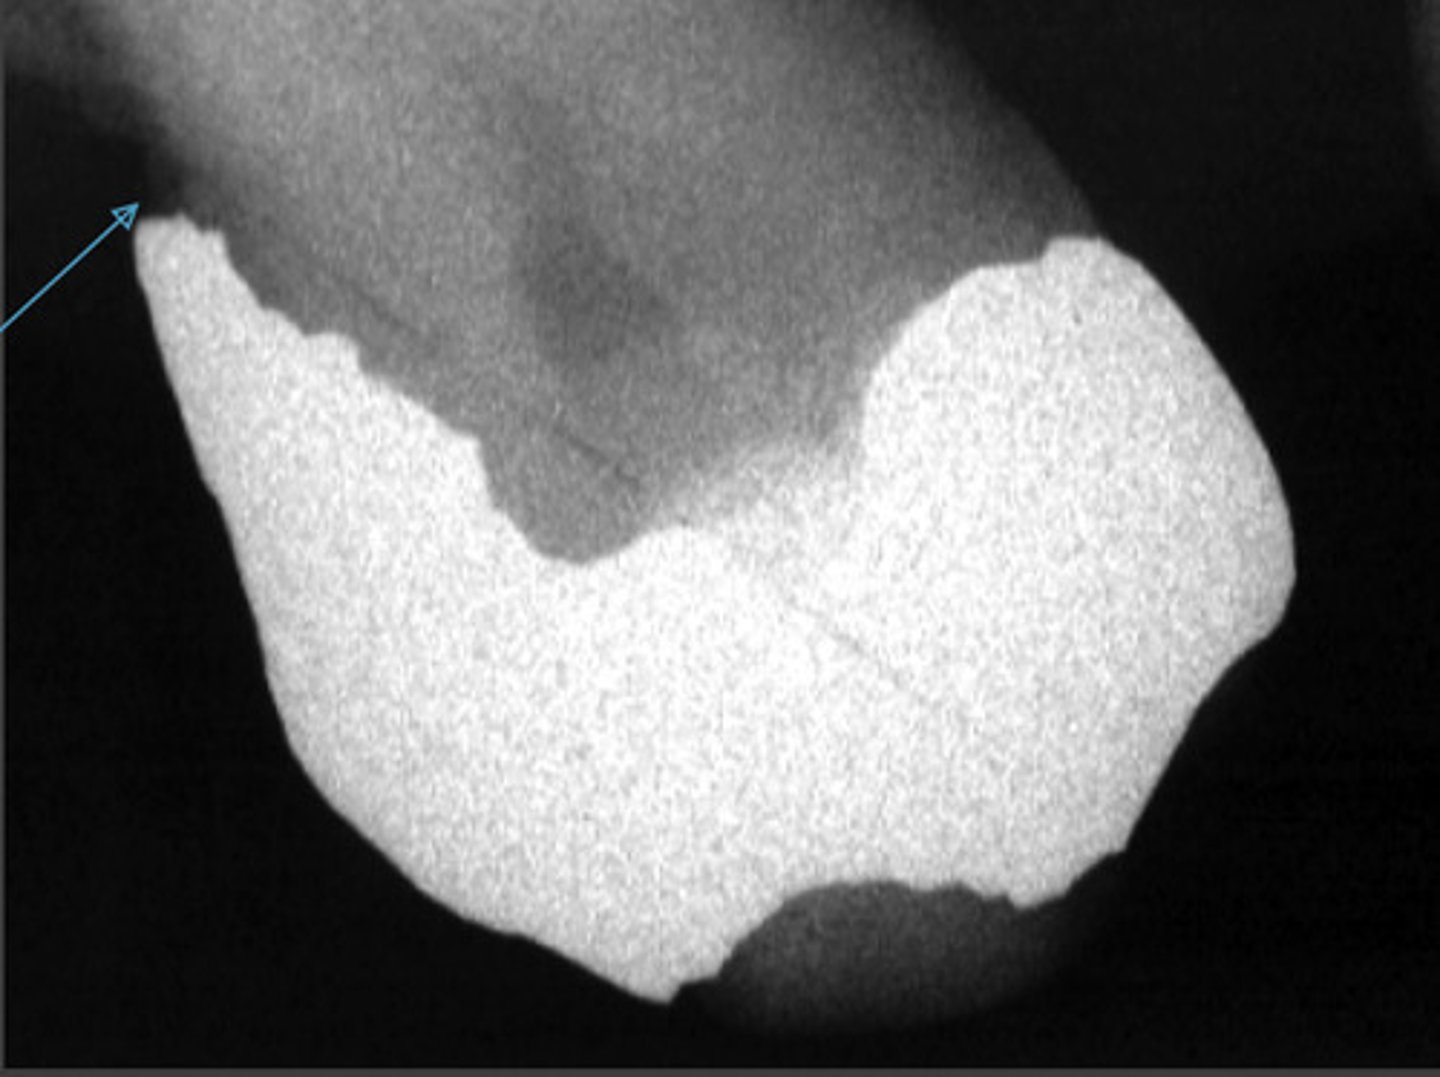

porcelain fused to metal crowns

full metal crowns

stainless steel crowns